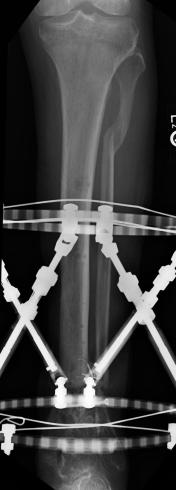

Postoperative (13th) images of left ankle

The image(s) displayed here were created following Liam's 13th surgery which was performed by Dr. Saunders. After a few hiccups getting

the surgery scheduled, Liam spent most of the September 13th afternoon in his 13th surgery. ;-) The surgery lasted about 5 hours and according

to the doctor, it was a good surgery. The 1st photo shows the new frame bracing that holds Liam's ankle together. The next series of photos show

various angles of the ankle and the rods that go from the frame into and through the left ankle. There was some concern that the swelling would

burst and allow for infection. Looks like we are now past that concern. Liam is still on antibiotics to ward of potential infection. The flesh

images show how the skin reacts to having the leg adjusted by the brace. The doctor has had to cut the skin to allow the rods to move freely.